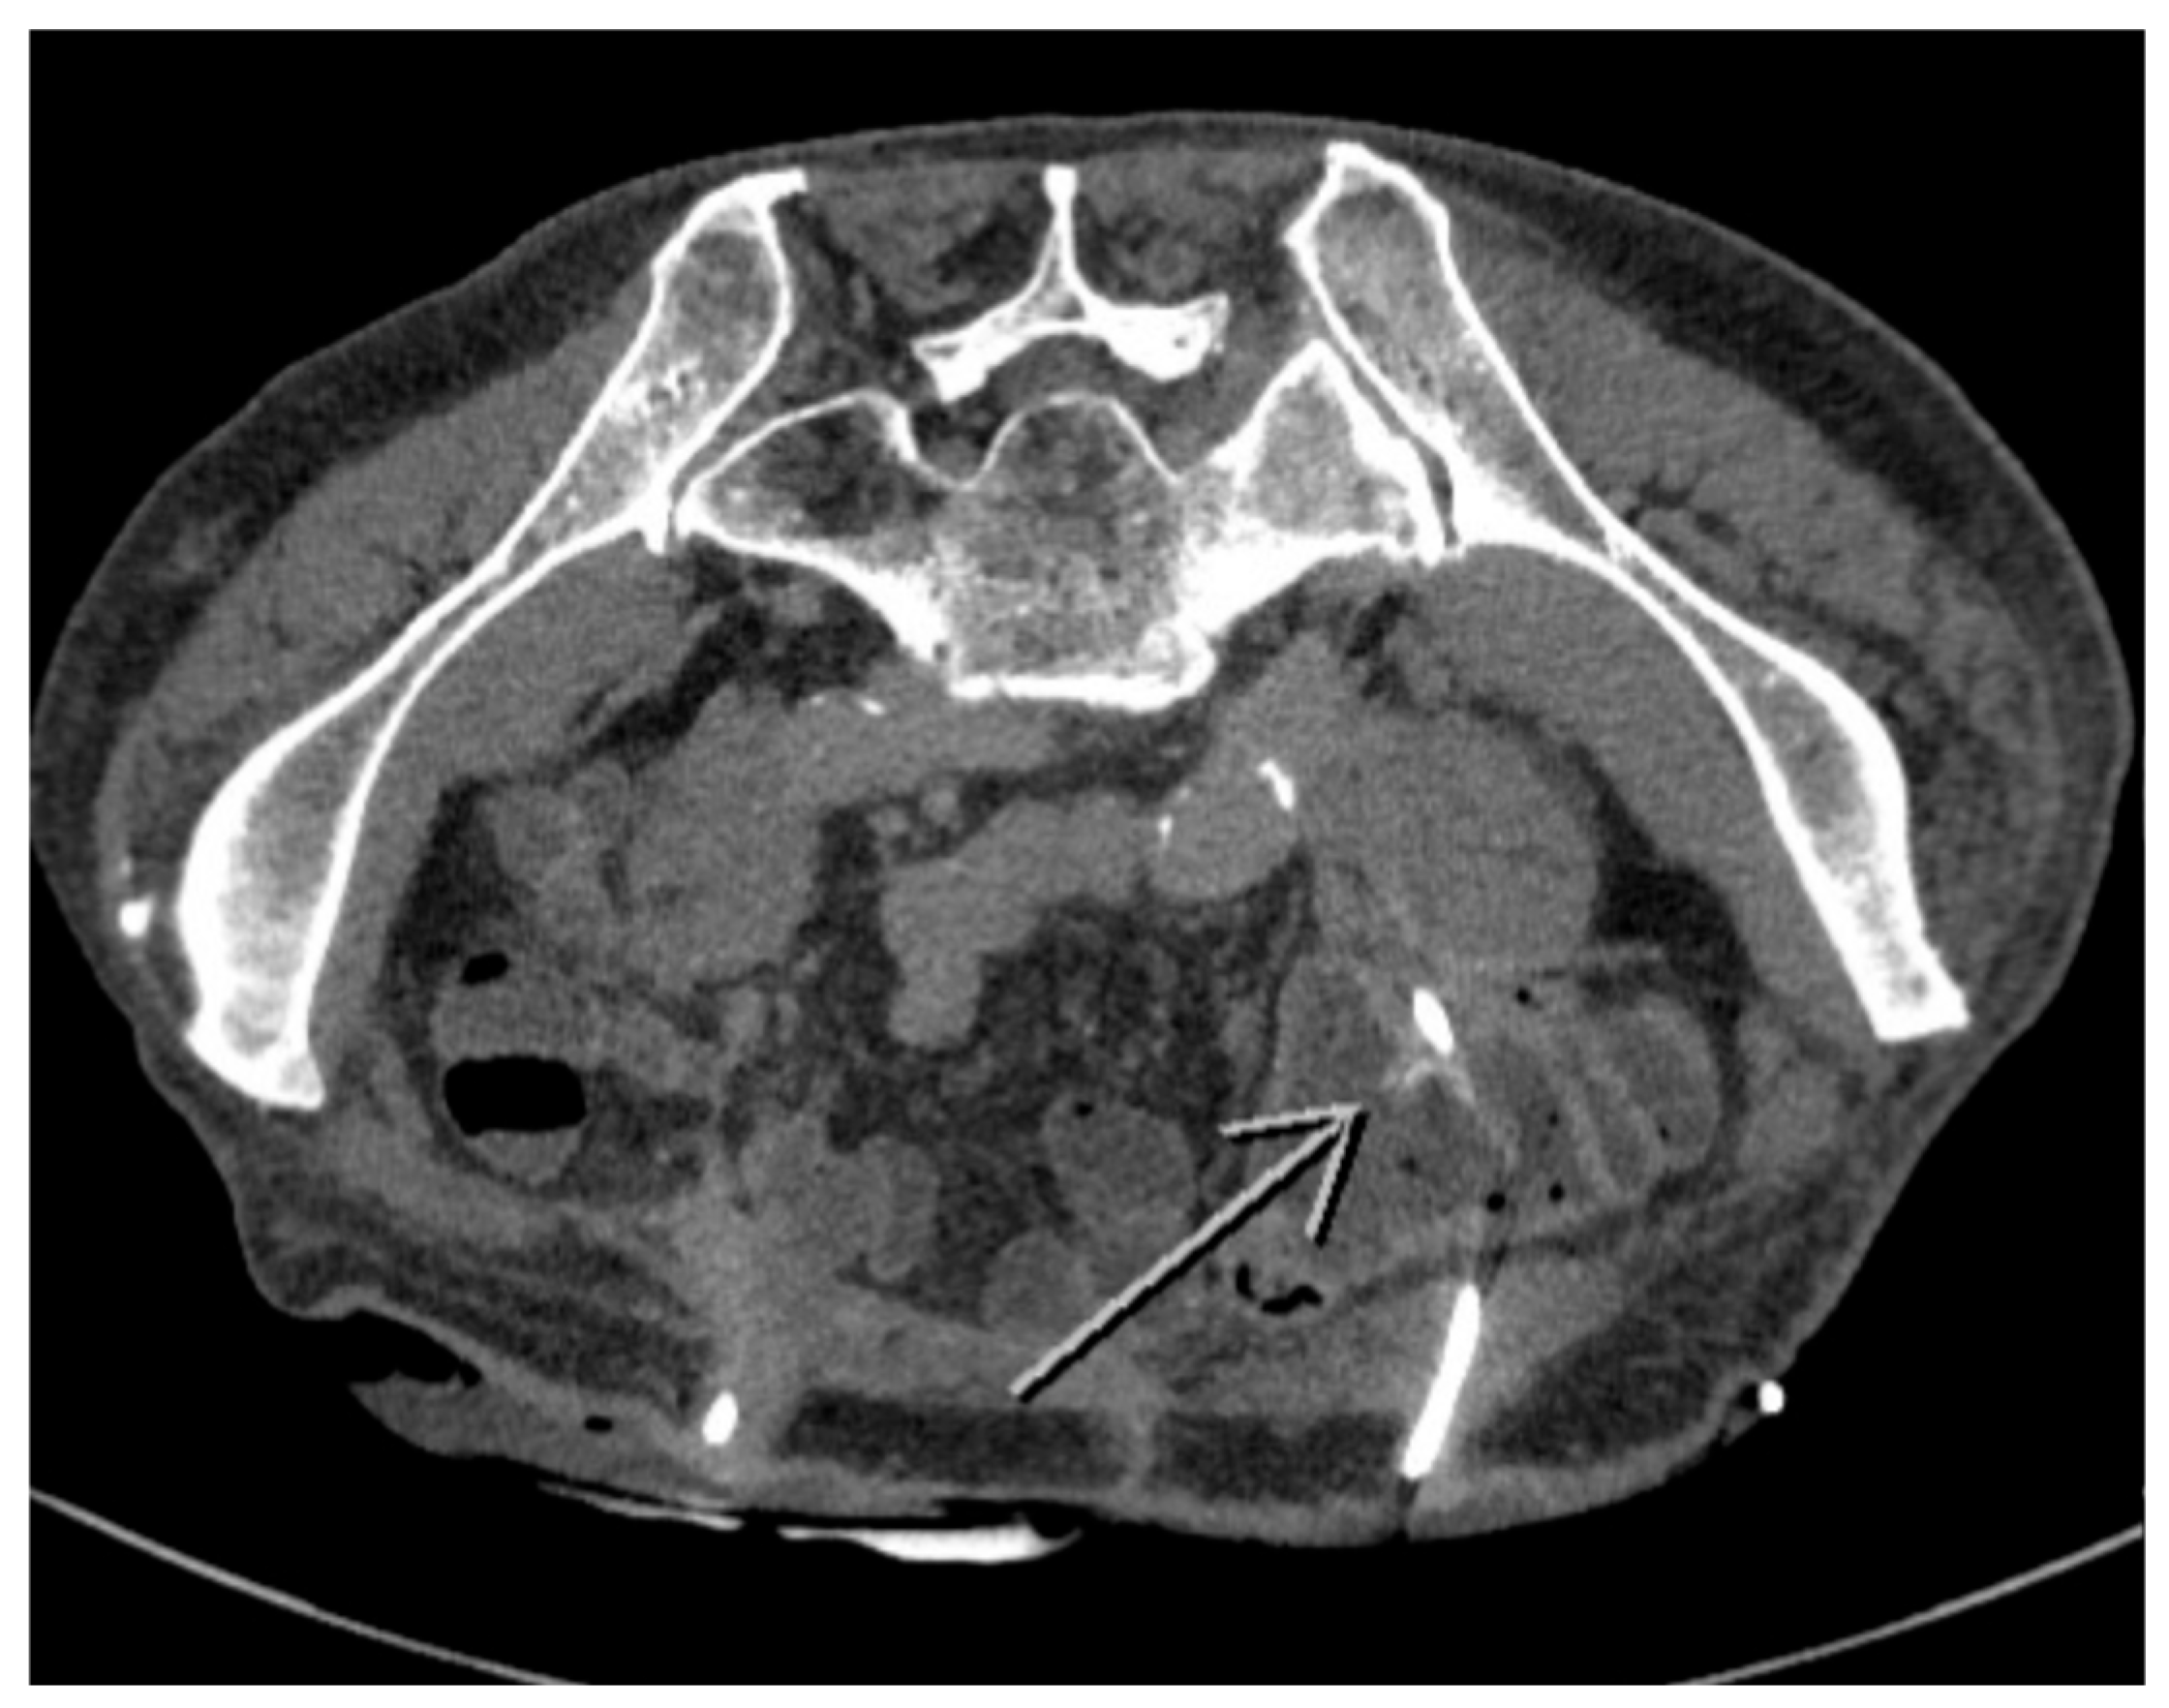

2. Case Presentation

2.1. Patient Characteristics and Clinical Findings